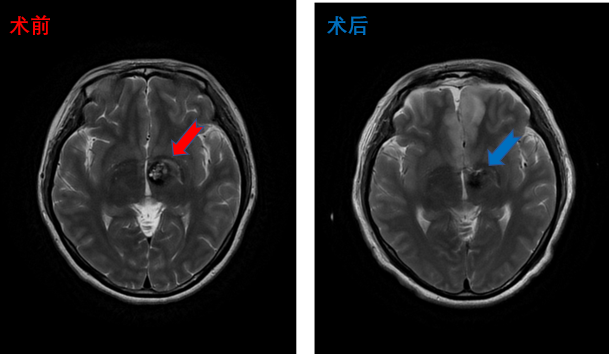

丘脑海绵状血管瘤患者影像,术后患者四肢活动正常